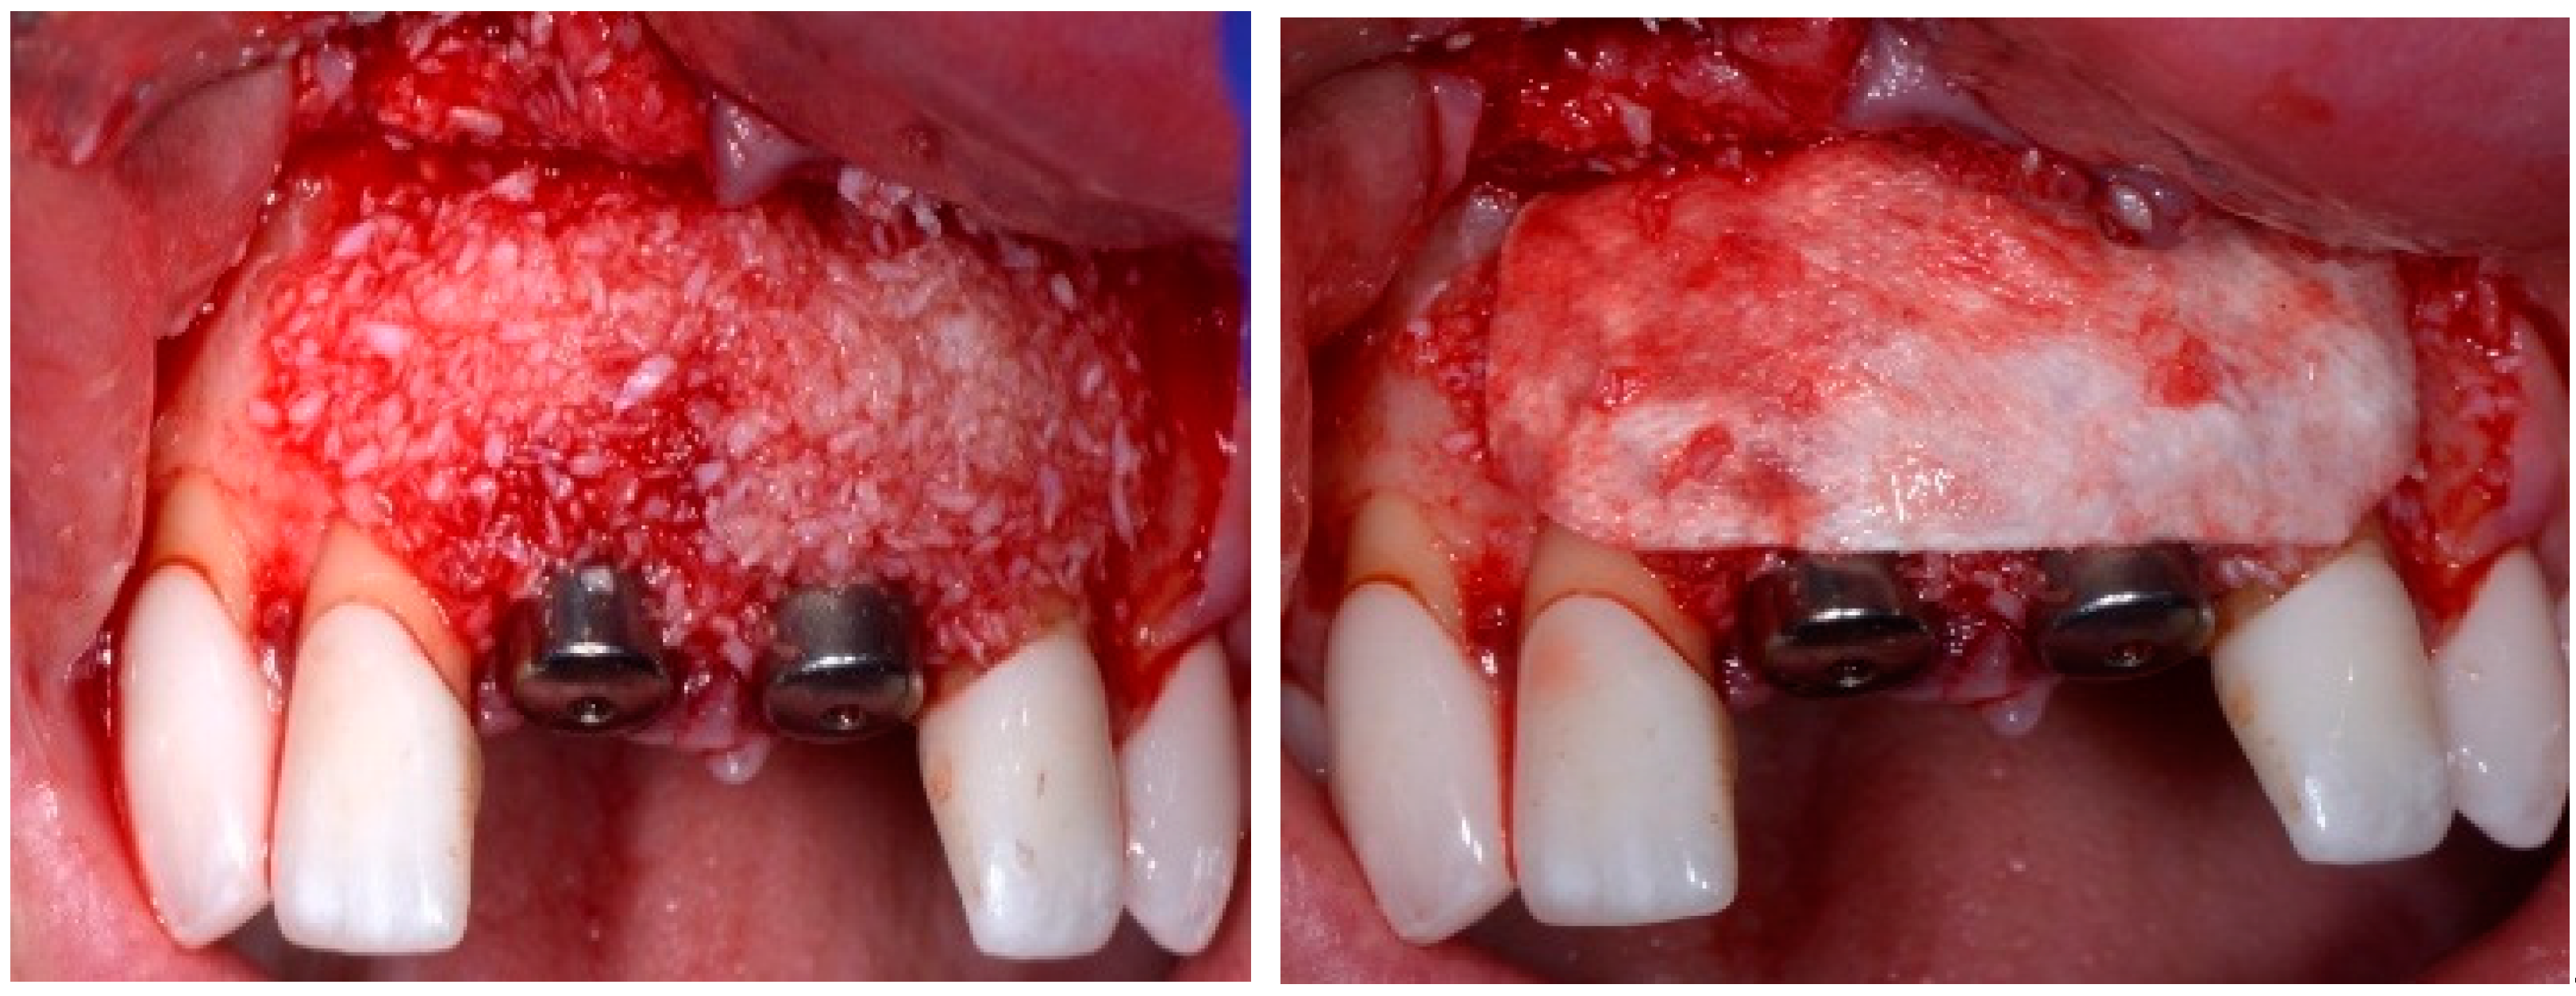

Before the graft and membrane is placed over the defect, a periosteal dissection must be performed to release flap tension to facilitate its coronal advancement and closure. The horizontal incision is made 1 mm deep into the periosteum, apical to the mucogingival junction, in a single plane along the length of the flap, connecting the two vertical releasing incisions. After the placement of this shallow incision, a micro-elevator is used to stretch within the incision line. This stretching not only releases the tension within the flap but also allows a more coronal advancement of the flap margin for eventual primary closure, minimizing postoperative incision line opening. This important step in flap management is performed before the placement of the graft material because the periosteal-releasing incision is associated with increased bleeding, which will complicate the graft, the membrane placement, and stabilization. A composite graft material consisting of allograft and xenograft in a 50/50 mix was placed in the gap between the implant and the socket wall over-contouring the facial wall defect (Figure 4). Two healing abutments were placed on the implants, followed by a bioabsorbable collagen membrane (Zmatrix, Osteogenics, Lubbock, TX 79424, USA) placed over the surgical area, which was closed with 5.0 polypropylene sutures (Figure 5). An Essex appliance, fabricated inhouse using a standard suck-down process, was inserted postsurgically. The implants were allowed to heal in a non-submerged environment for a period of 6 months.

Figure 4.

Clinical view post graphing.